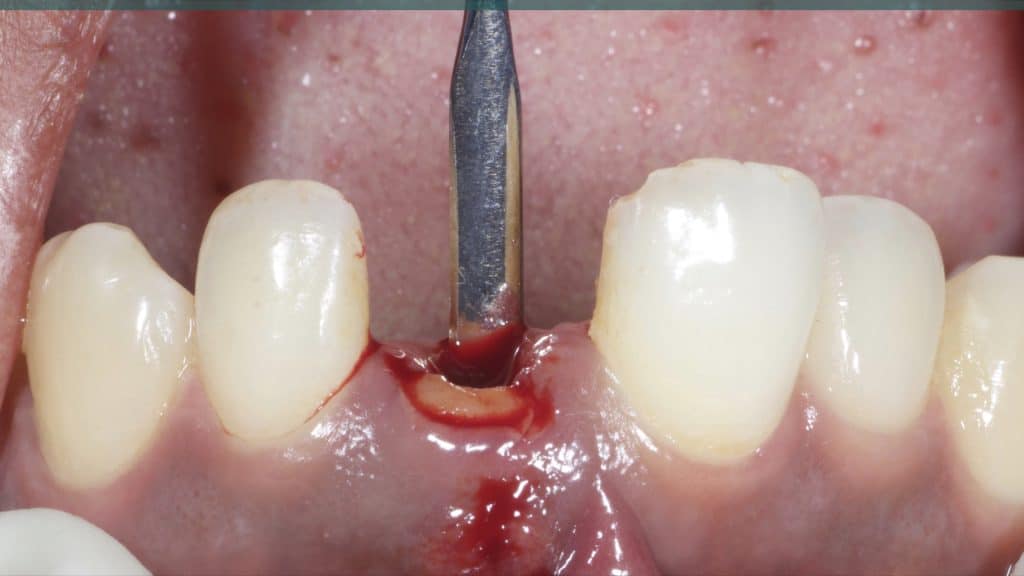

20 days post-op after suture removal